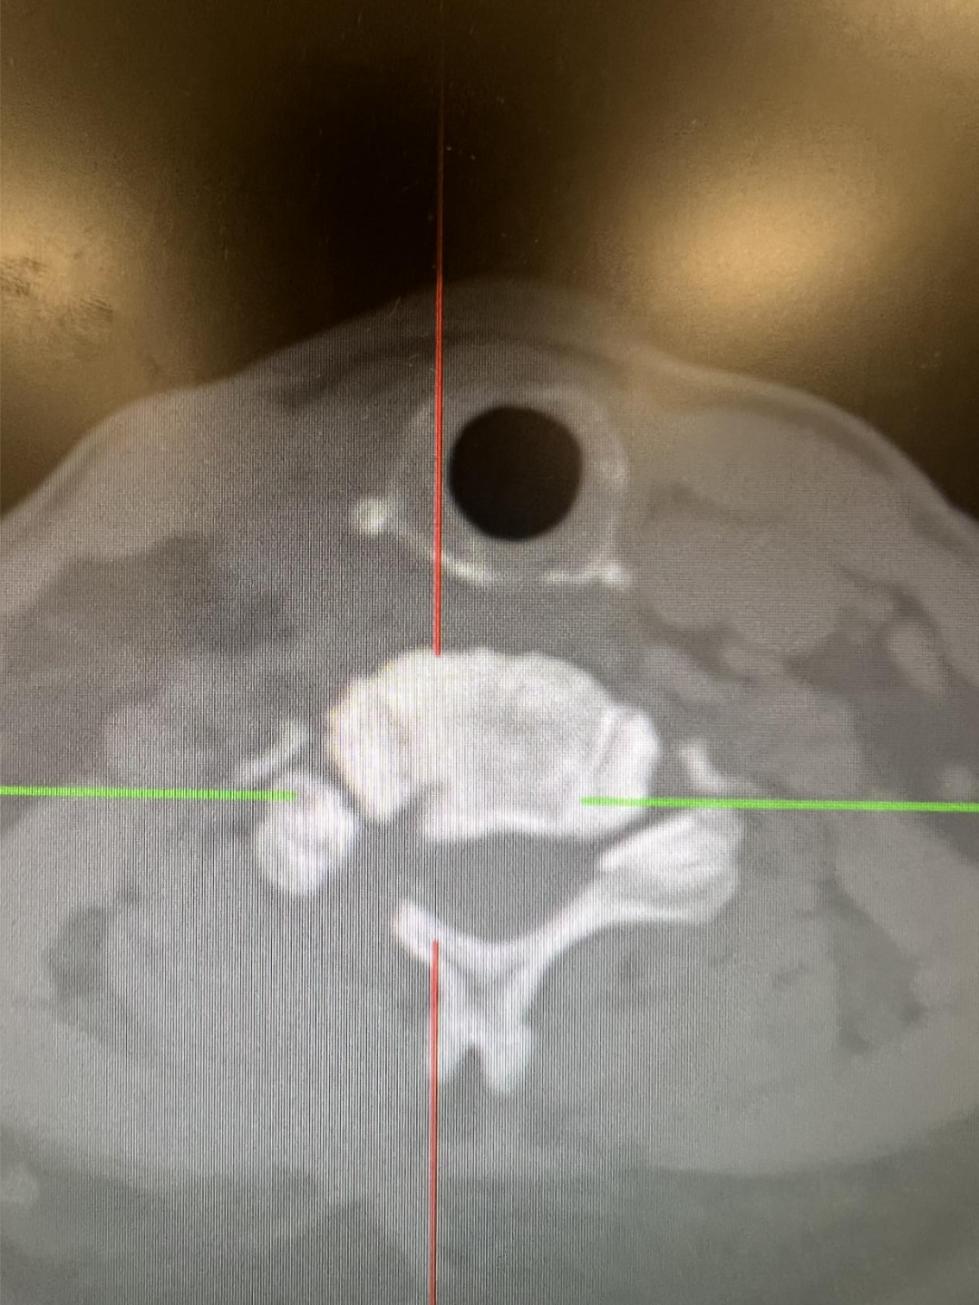

杨俊松副主任医师接诊后结合患者病史、体征和影像学资料指出,患者椎间盘突出钙化形成骨赘+神经根明显受压+椎间孔高度塌陷,建议手术干预。

脊柱病医院院长郝定均及脊柱病医院腰椎病区主任刘团江查房后指出:患者骨赘生长及神经根受压明显,且曾有过两次甲状腺手术经历,建议采用内镜下的颈椎后路keyhole手术。

为了避免手术中高速磨钻磨除骨赘时可能损伤脆弱的脊髓。杨俊松借助超声骨刀微米级震动不影响软性脊髓、神经组织但可以将骨性组织直接气化的特性,完整去除骨赘。

手术结束后当天患者症状明显缓解。复查影像资料显示神经减压良好、骨赘完全去除。

术后影像资料